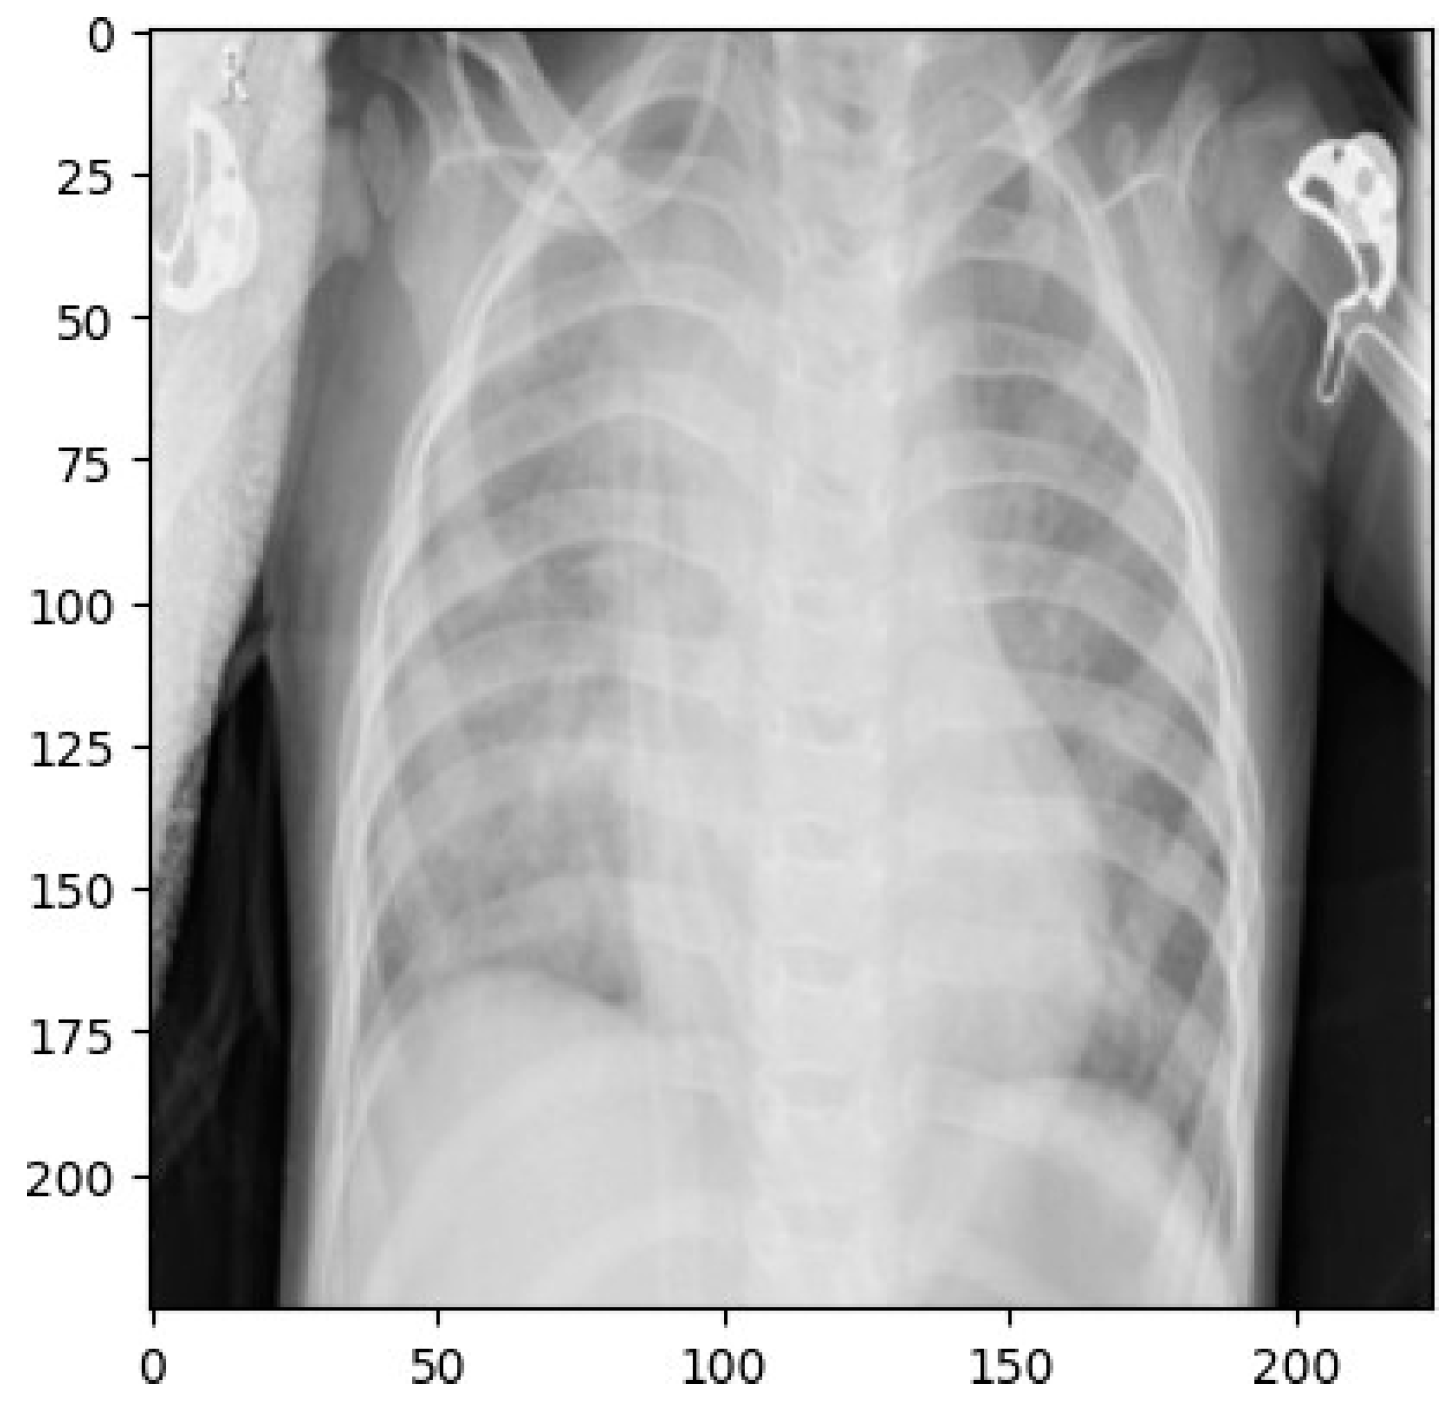

2.2. Dataset

2.4. Image Enhancement Techniques

Resizing

2.5. Normalization